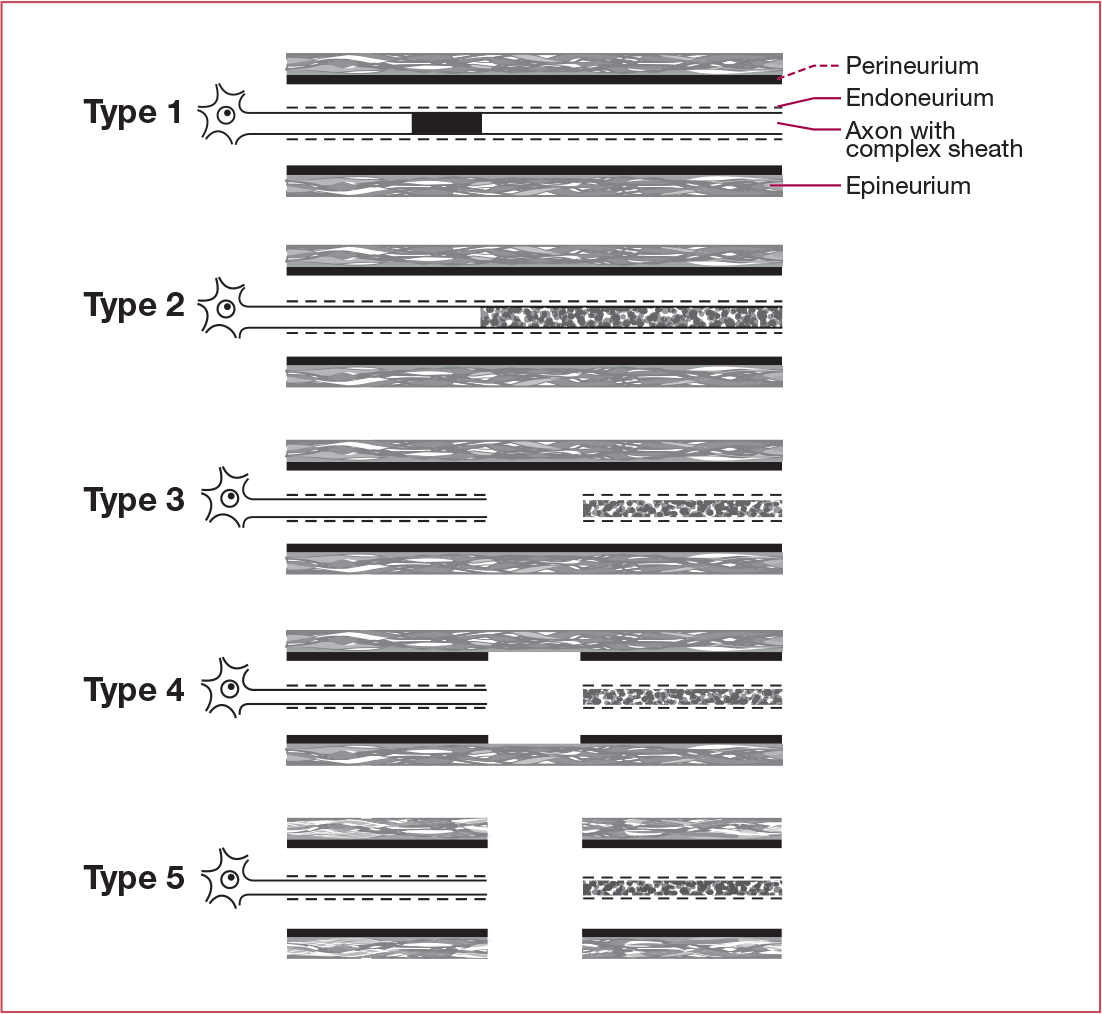

Describe the Sunderland Classification of Nerve Injury

- Neurapraxia (conduction block)

- Axonotmesis (Axon damage(

- Axon and Endoneurium injury

- Axon, Endoneurium, and Peineurium injury (only Epineurium intact)

- Neurotmesis (complete nerve transection)